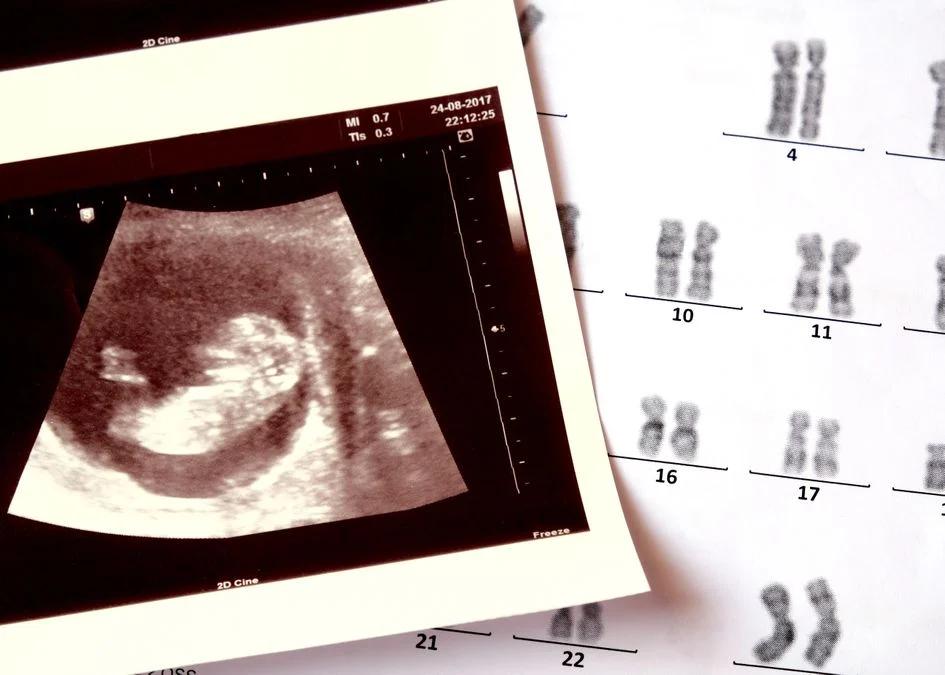

Bluttests vor der Geburt sind medizinische Untersuchungen, die während der Schwangerschaft durchgeführt werden, um das Blut der Mutter auf bestimmte Marker zu untersuchen. Diese Marker können Hinweise auf die Gesundheit des ungeborenen Kindes geben, wie zum Beispiel auf Chromosomenstörungen, genetische Erkrankungen oder Infektionen. Die Ergebnisse dieser Tests können den Ärzten helfen, die Schwangere und ihr Kind optimal zu betreuen und gegebenenfalls frühzeitig Maßnahmen zu ergreifen.

- Ersttrimester-Screening: Dieser Test wird in der Regel zwischen der 1und 1Schwangerschaftswoche durchgeführt. Er untersucht das Blut der Mutter auf bestimmte Hormone und Proteine, die Hinweise auf das Risiko für Chromosomenstörungen wie Trisomie 21 (Down-Syndrom), Trisomie 18 (Edwards-Syndrom) und Trisomie 13 (Patau-Syndrom) geben können.

- NIPT (Nicht-invasiver Pränataltest): Dieser Test wird in der Regel ab der Schwangerschaftswoche durchgeführt. Er untersucht die DNA des Fötus, die im Blut der Mutter zirkuliert. Der NIPT kann das Risiko für bestimmte Chromosomenstörungen wie Trisomie 21, Trisomie 18 und Trisomie 13 sowie für andere genetische Erkrankungen wie das Klinefelter-Syndrom und das Turner-Syndrom feststellen.